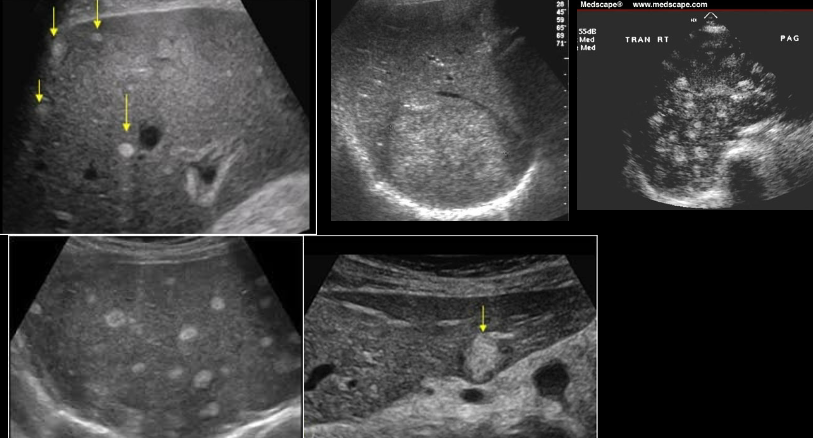

echinococcal cyst

echinococcal cyst (squiggle lines is the water lily sign)